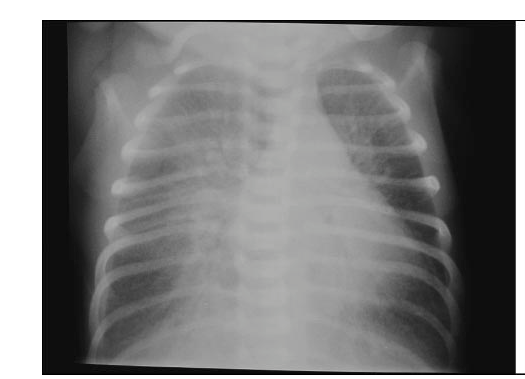

An overview of the systematic reviews of therapies for TTN has recently been published (Bruschettini M, et al. Interventions for the management of transient tachypnoea of the newborn – an overview of systematic reviews. Cochrane Database Syst Rev. 2022;2(2):CD013563). There are numerous problems in studying TTN, in part because of a lack of widely accepted diagnostic criteria, but this is an area wide open for research, for which large amounts of resources are currently used. The image above, I would suggest, is classic for TTN, but there is a great deal of inter-rater variability in the diagnosis even among radiologists.

I have long been sceptical of the value of CPAP and non-invasive ventilation in TTN, CPAP is great for low volume lung diseases, but lung volumes on chest x-ray of TTN are often increased (as in the radiograph above), and whether external positive pressure actually improves lung liquid clearance and clinical resolution is uncertain. This should be a research priority, shortening the duration of intensive care for these babies would benefit many thousands of families, and could save significant resources.